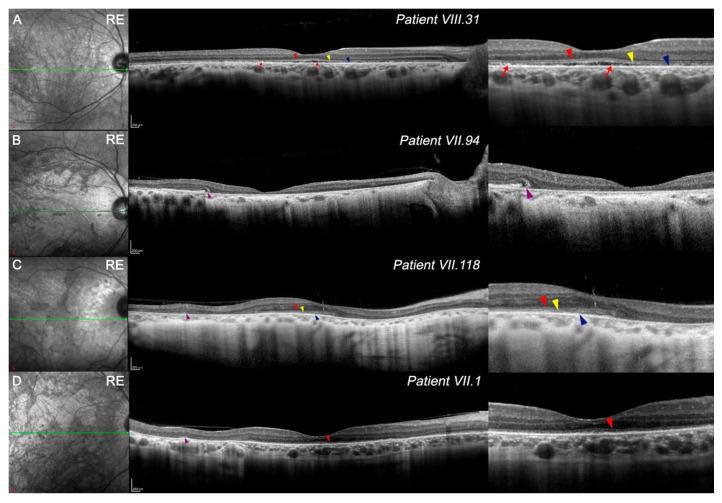

Choroidal dystrophies comprise a group of chorioretinal degenerations. However, the different findings observed among these patients make it difficult to establish a correct clinical diagnosis. The objective of this study was to characterize new clinical findings by optical coherence tomography (OCT) and optical coherence tomography angiography (OCTA) in these patients. Four family members with a gene mutation (p.Arg195Leu) were included. OCT was performed at the macula, and the thickness of the outer and inner retina, total retina, and choroid was measured. The features of the vascular network were analyzed by OCTA. Patients showed a decreased outer nuclear layer in the avascular area compared with the controls. Two patients presented greater foveal and parafoveal degeneration of the outer retina, whereas the most degenerated area in the rest was the perifovea. Disruption of the third outer band at the foveola is one of the first-altered outer bands. Slow blood flow areas or capillary dropout were main signs in the deep capillary plexus. Microaneurysms were frequently observed in less degenerated retinas. Vascular loops and intraretinal microvascular abnormalities (IRMAs) were present in the superficial plexus. Extensive degeneration of the choriocapillaris was detected. Phenotypic differences were found between patients: two showed central areolar choroidal dystrophy and the rest had extensive chorioretinal atrophy. These signs observed in OCT and OCTA can help to more appropriately define the clinical disease in patients with choroidal dystrophies.

脉络膜营养不良包括一组脉络膜视网膜变性疾病。然而,这些患者中观察到的不同表现使得难以做出正确的临床诊断。本研究的目的是通过光学相干断层扫描(OCT)和光学相干断层扫描血管造影(OCTA)来描述这些患者的新临床特征。纳入了四名携带 基因突变(p.Arg195Leu)的家庭成员。在黄斑区进行OCT检查,测量视网膜外层和内层、整个视网膜以及脉络膜的厚度。通过OCTA分析血管网络的特征。与对照组相比,患者无血管区的外核层变薄。两名患者黄斑和黄斑旁区域的视网膜外层出现更严重的变性,而其余患者最严重的变性区域是黄斑周围。黄斑小凹处第三外带的破坏是最早发生改变的外带之一。深部毛细血管丛的主要表现为血流缓慢区域或毛细血管缺失。在变性较轻的视网膜中经常观察到微动脉瘤。浅表血管丛中存在血管袢和视网膜内微血管异常(IRMA)。检测到脉络膜毛细血管广泛变性。患者之间存在表型差异:两名患者表现为中心性晕轮状脉络膜营养不良,其余患者则有广泛的脉络膜视网膜萎缩。在OCT和OCTA中观察到的这些特征有助于更准确地界定脉络膜营养不良患者的临床疾病。